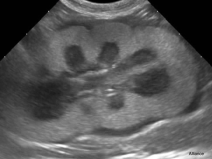

• Journée Echographie abdominale Capbreton 2022

Les consultations pour insuffisance rénale sont nombreuses alors que l’analyse urinaire et les examens biologiques sont bien souvent insuffisants pour en déterminer la cause. L’examen échographique des reins et des uretères est alors un complément indispensable.

Les consultations pour strangurie, dysurie et hématurie sont également un grand classique de nos salles de consultations et un...

Le 23 septembre 2022

Capbreton (40130)

Imagerie Médicale

Aquitaine

1366